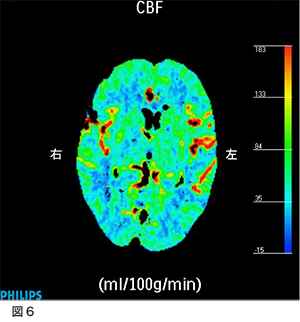

脳血流検査(CT perfusion)図6

術後検査として造影剤を使用したCTで血流評価をしました。この結果、脳血流量の左右差はほとんど消失しています。